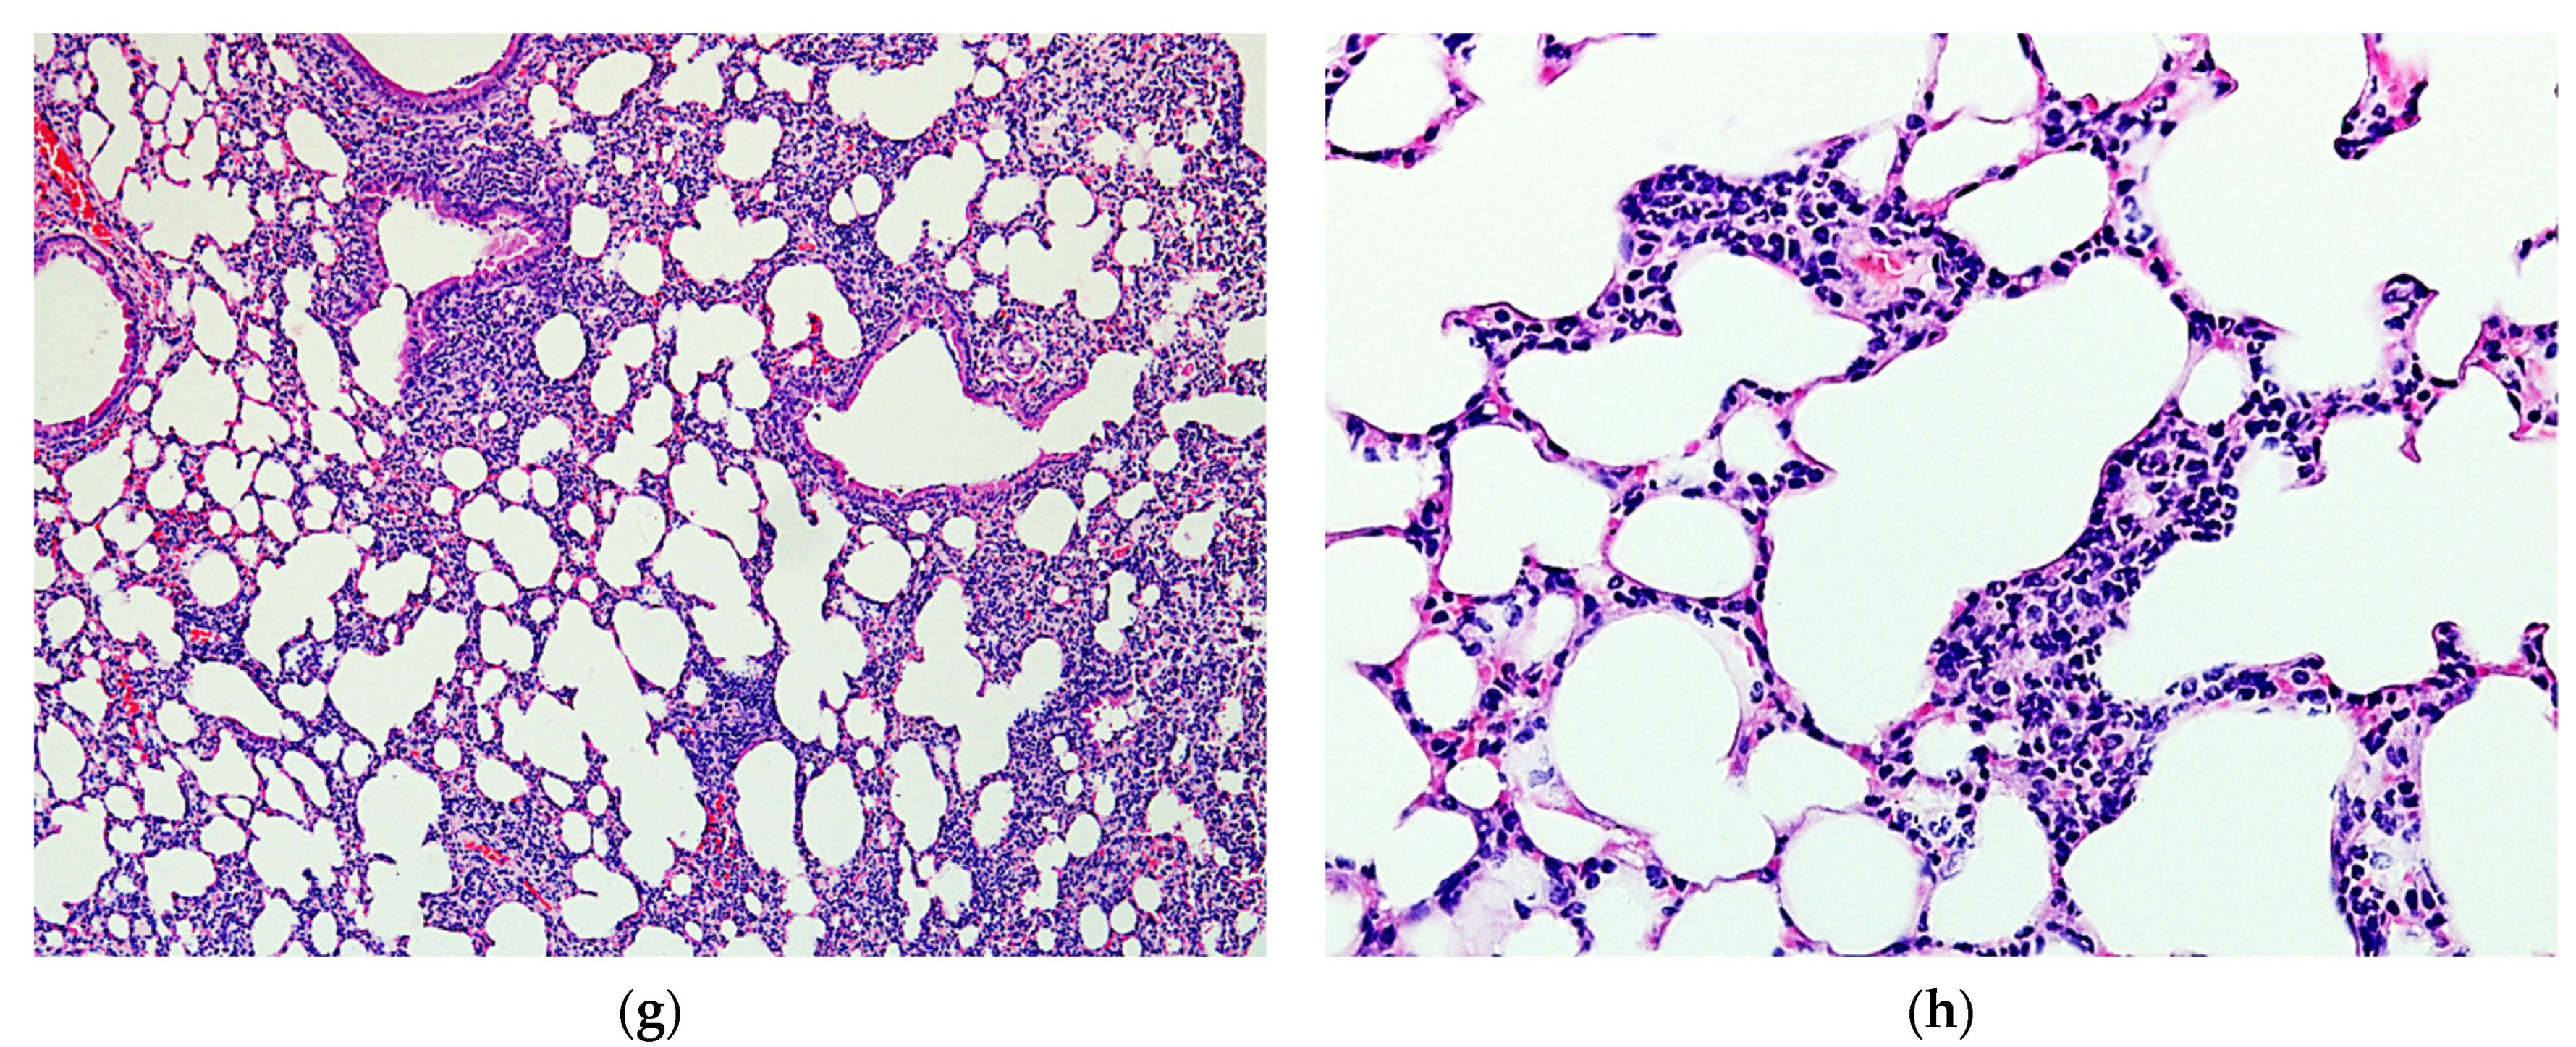

2.4. Protective Activity of 9g in LPS-Induced Acute Lung Injury

4.13. Histological Study